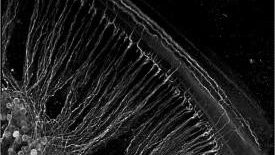

Broadly, our aim is to translate discoveries about transmembrane receptor and ion channel signal transduction, into new platforms for treatment of neurological disorders. Our research program focuses on neuroprotection and repair in sensori-motor pathways. A principal area of research concerns the molecular and cellular basis of hearing loss (auditory neuroscience), where we investigate cell signalling that contributes to sensory hair cell and neuronal death due to noise and aging (including synaptic neuropathy). Study of neural development and synaptic plasticity in the auditory system informs on gene-targets for neural repair.

This research has an applied arm with respect to bionics such as the cochlear implant, and more broadly in developing neural interfaces with the brain. Within the brain, we are investigating neural plasticity associated with driven input (e.g. via the cochlear implant) and mechanisms for protection and repair of the nervous system (such as ischaemic brain injury, a model of stroke). Hearing loss is the most prominent sensory disability in our society. Stroke is the third highest killer and the most disabling for survivors. Our work is supported by national and international collaborations and funding.

BaDGE® gene augmentation to improve the ‘Bionic Ear’: We are working to improve hearing and speech outcomes for cochlear implant recipients. underpinning the BaDGE® gene augmentation platform technology which is migrating to a first-in-human clinical trial to regenerate the cochlear nerve and ‘close the neural gap’ with cochlear implants. This work is supported by the CINGT program and includes co-investigators from the UNSW Biomedical Engineering Institute, the Bionics Institute (U. Melbourne), Dept. Otolaryngology U. Sydney, Sydney Cochlear Implant Centre, Macquarie University Hearing Hub and industry partner Cochlear Ltd.

- Hearing protection conferred by P2X2 receptor signaling in the cochlea

- Physiological significance of transient receptor potential (TRPC3) ion channels in the cochlea